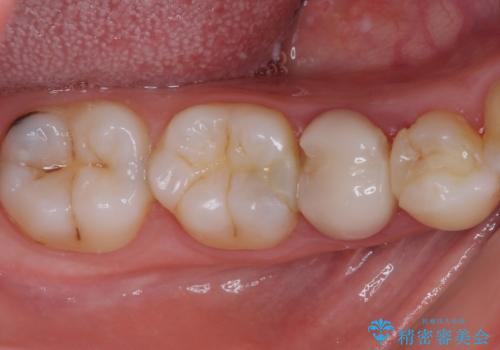

- 神経を抜く処置の後に装着したプラスチックのクラウンが外れてしまったとのことで来院された患者様です。

患者様自身、神経の取り除かれた歯はしっかりと製作されたクラウンを装着するべきと理解していただいていたため、オールセラミッククラウンにて補綴治療することとしました。

丈夫なクラウンを装着できただけでなく、形態や色調も自然に仕上げることができました。